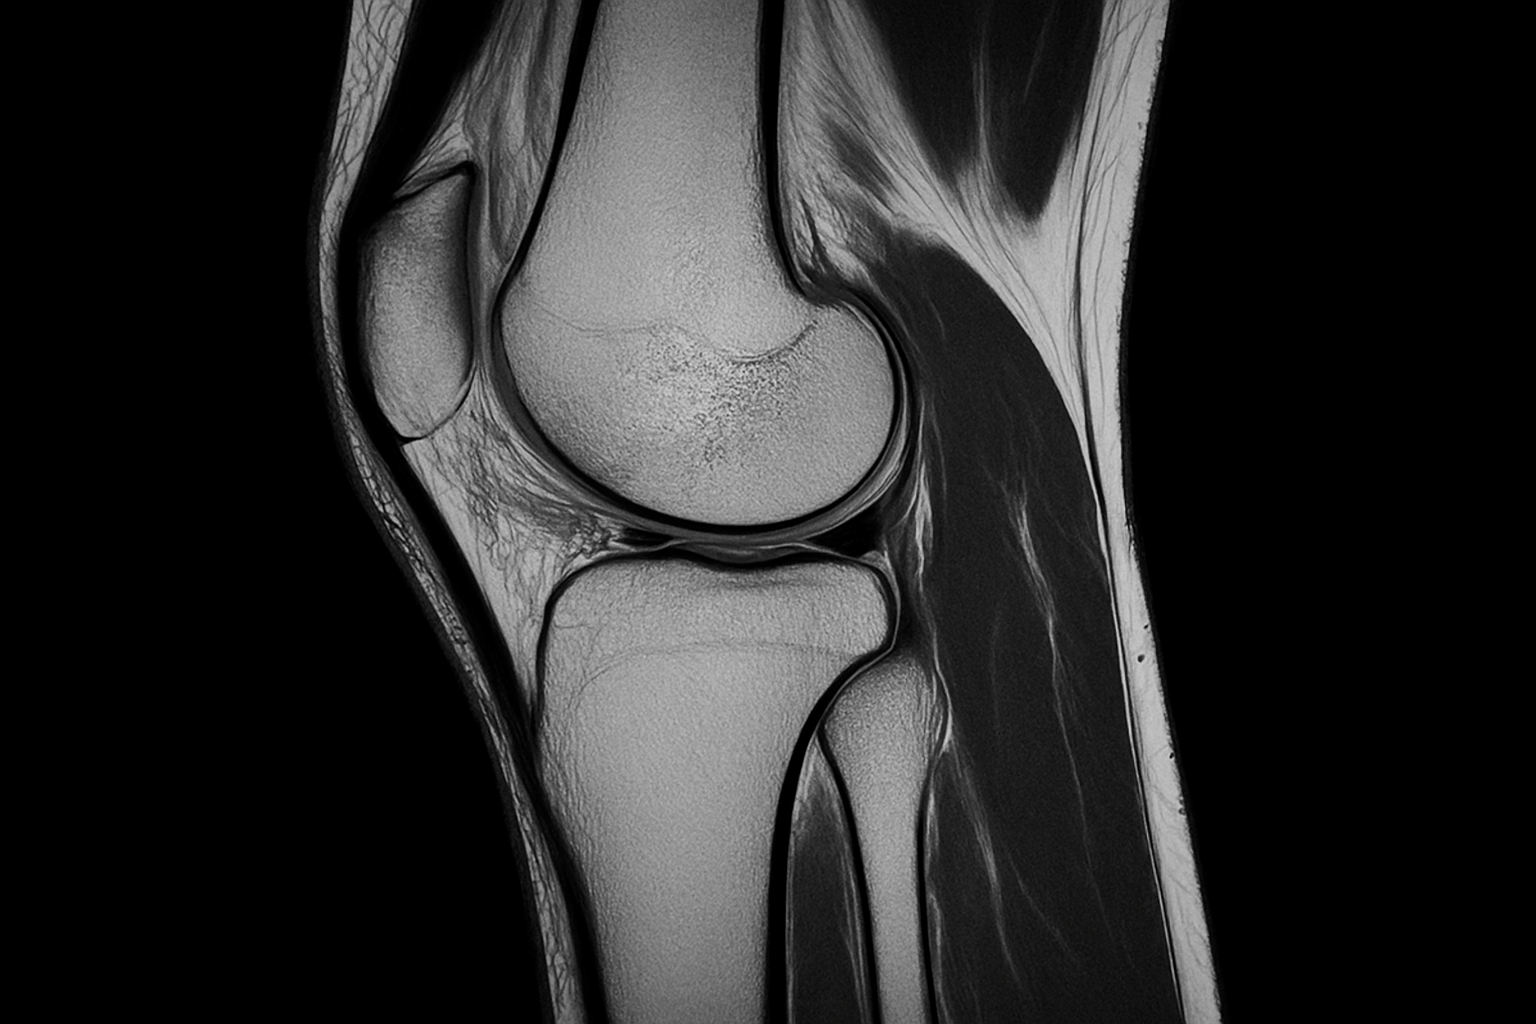

Применение этого метода позволяет получить графическое изображение прилегающих мягких тканей, окружающих кости, тем самым существенно увеличивает эффективность постановки диагноза, выявления нарушений для дальнейшего назначения лечения.

Проводиться МРТ суставов в лежачем положении с использованием специальных диагностических катушек. Для диагностики определенного сустава используется индивидуальная катушка, которая изготовлена с учетом особенностей сустава. Благодаря особенной форме катушки и ее электронному содержимому, возможно получить точное изображение структуры исследуемого сустава.

Получение многоплоскостных изображений в дополнении с контрастностью мягких тканей, позволяют увидеть максимально полную картину как внутренних, так и внешних структур суставов: сухожилья, костный мозг, жировая ткань, хрящ, мышцы.